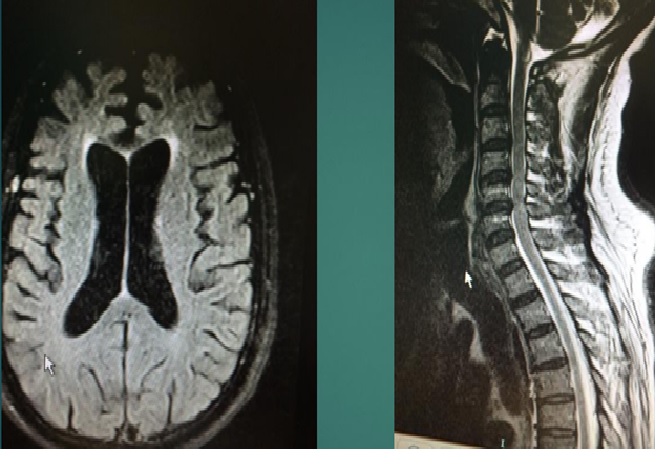

MRI cột sống cổ và não có gado.

MRI não : có teo não thùy trán 2 bên, không có nhồi máu hay xuất huyết não,

MRI tủy: lồi đĩa đệm nhẹ C3-4,C5-6 không chèn ép tủy, không có dị dạng Chiari

- MRI cột sống cổ và não

Đối với ALS, MRI có thể cho thấy tăng tín hiệu dọc theo bó vỏ tủy sống (tủy sống trước, bụng thân não và chi sau của bao trong) do sự thoái hóa của nơ-ron vận động trên.